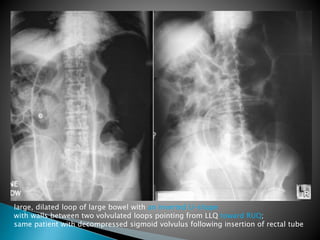

large, dilated loop of large bowel with an inverted U-shape

with walls between two volvulated loops pointing from LLQ toward RUQ;

same patient with decompressed sigmoid volvulus following insertion of rectal tube

large, dilated loopof large bowel with an inverted U-shape with walls between two volvulated loops pointing from LLQ toward RUQ; same patient with decompressed sigmoid volvulus following insertion of rectal tube